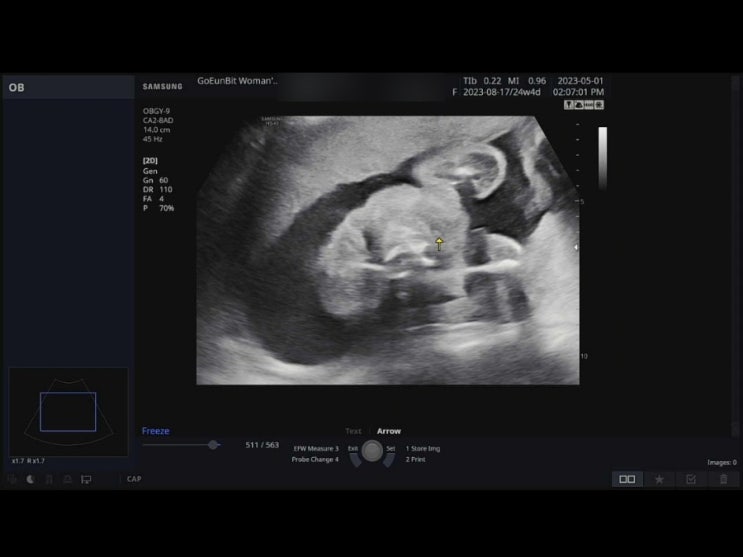

[28주0일] 입체초음파 보고왔어요 :D (@강동고은빛)

2023.05.25 28주 0일. 오늘은 입체초음파를 보는 날이에요. 입체초음파는 보통 27주~30주 사이에 보는데, 2...